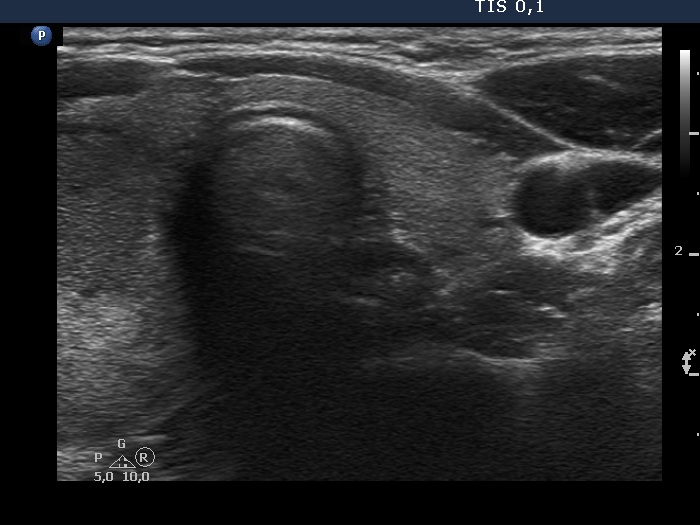

Ultrasonography. The thyroid was echonormal. There was a heterogeneous nodule in the right lobe. The lesion contained roughly equal proportions of echonormal and moderately hypoechoic portions. The nodule had a thin halo and presented perinodular blood flow.